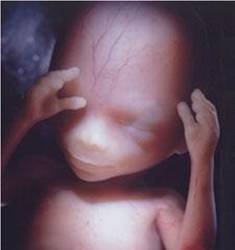

13 недель

Вот и наступил второй триместр, ура!!! Мы уже на четвертом месяце))) Что имеем к этому дню: Опять начала болеть грудь, я уже было обрадовалась, что прошло, ан нет. Не тошнит))) Еще больше бегаю в туалет, так что далеко от дома не отходим... У врача больше не была в связи с карантином, пропустила прием 18 числа. Ждем, когда начнут пускать беременных в ЖК, может уже на след. неделе))) Животика нетю. Вернее, он есть где-то внутри, я чувствую, но визуально еще ничего не заметно. Вот пожалуй и все. А так сейчас выглядит мой малышик

Написано, что уже можно определить, мальчик это или девочка)))

Написано, что уже можно определить, мальчик это или девочка)))